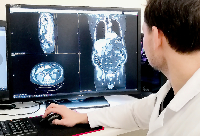

Магнитно-резонансная томография (МРТ):один из самых эффективных методов диагностики заболеваний